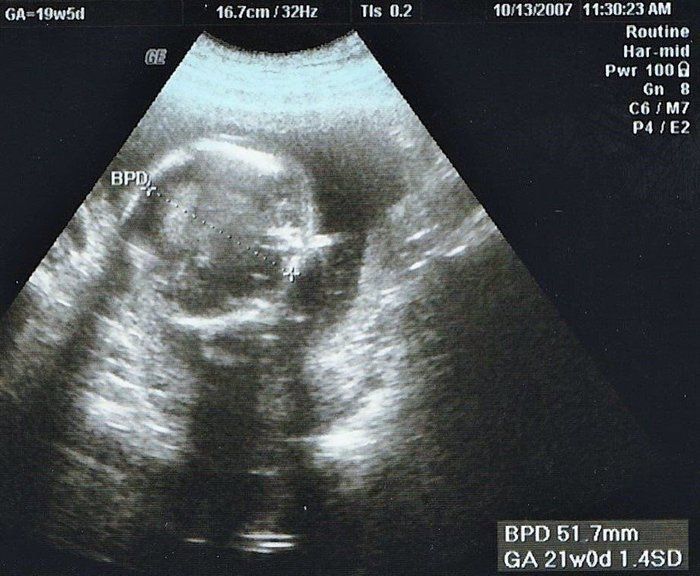

まきさんの妊娠19週目のエコー写真 赤ちゃんの心室や膀胱の様子もエコーで確認できました。

妊娠19週目。性別がわかるかもしれないということで、主人も一緒について来た健診のときのエコー写真です。エコーを見せてもらって、先生から「心臓の部屋は4つ。膀胱におしっこも溜まっているから、腎臓にも異常なし。背骨もしっかりしていて体重等も標準。いい子です」と言っていただいてひと安心。帰りの車で主人に「先生、女の子って言っていたね」と言われてビックリ!聞き逃していた…。主人曰く「先生は女の子でまちがいないとも言っていたよ」とのこと。帰りに本屋さんに寄って、女の子の名前辞典を買いました。